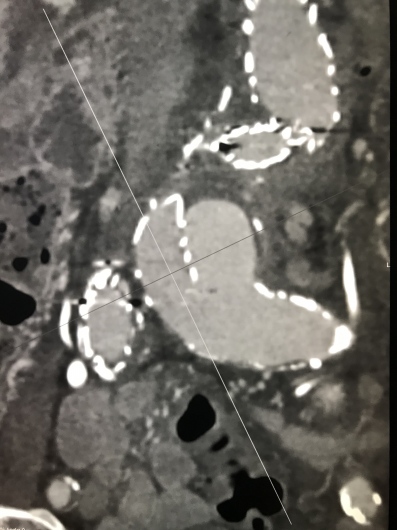

Dirigente Medico di ruolo presso U.O.C. Chirurgia Vascolare ed Endovascolare Ospedale San Giovanni di Dio e Ruggi d’Aragona di Salerno. Pratica attività ambulatoriale, laboratorio di diagnostica ultrasonografica, diagnostica angiografica e attività di sala operatoria (chirurgia open ed endovascolare). L’attività chirurgica tradizionale ed endovascolare comprende il trattamento delle lesioni stenotiche/ostruttive dei tronchi sovraortici (carotidi), lesioni stenotiche/ostruttive delle arterie periferiche e viscerali, degli aneurismi dell’aorta e aneurismi periferici e viscerali (sia in elezione che in urgenza), inoltre l’attività chirurgica comprende il trattamento della patologia venosa (vene varicose/varici) secondo le tecniche chirurgiche classiche (es. stripping) e moderne (laser, radiofrequenza, scleroterapia maggiore), scleroterapia minore di teleangectasie e vene reticolari (estetica vascolare).